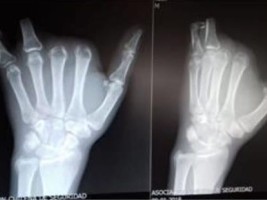

The accident occurred on November 16 in Los Angeles, in the Nuñble area, more specifically in the premises of Serfocom company specializing in forestry services and construction. Dominique Melvin claims that the company would not have given him the necessary instructions to safely operate a conveyor that amputated him in the accident four finger.

Reacting to the accident, the employer offered the Haitian worker compensation of 500,000 pesos (± 743.25 dollars) and return tickets to Haiti. This offer, described as "ridiculous" by Melvin , led him, with the help of a lawyer specialized in labor law, to bring an action for damages for occupational injuries, against the company Serfocom, before the second court of labor of Los Angeles.

Melvin would seek in his lawsuit the payment of 140 million pesos (± 208,110 dollars) for moral damages and 131 million pesos for loss of earnings (± 195,219 dollars).